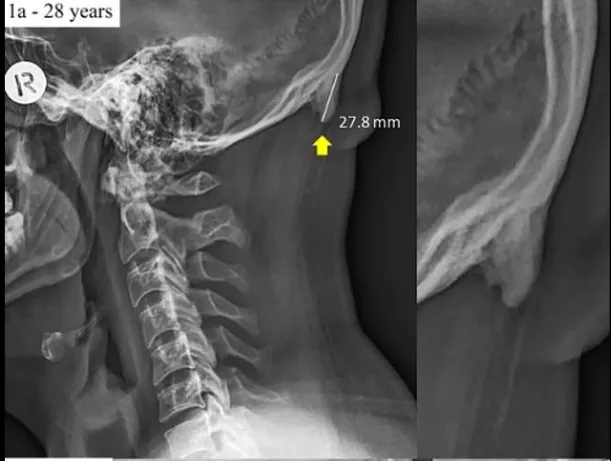

Cụ thể, trường Đại học Sunshine Coast, Queensland, Úc mới đây đã công bố các hình ảnh chụp x-quang, chứng minh phần xương chẩm của hộp sọ con người có xu hướng phát triển nhiều hơn, do họ cúi đầu quá lâu lúc dùng điện thoại hay máy tính.

Hộp sọ của một người 28 tuổi có phần xương chẩm phát triển bất thường

Theo những người thực hiện nghiên cứu, trước đây hiện tượng kể trên rất hiếm gặp. Tuy nhiên, ngày càng có nhiều trường hợp được ghi nhận hơn, những người có phần xương chẩm phát triển bất thường trên hộp sọ thường có độ tuổi từ 18 đến 30 tuổi, những người thương dành khá nhiều thời gian cắm mặt vào màn hình smartphone, máy tính.